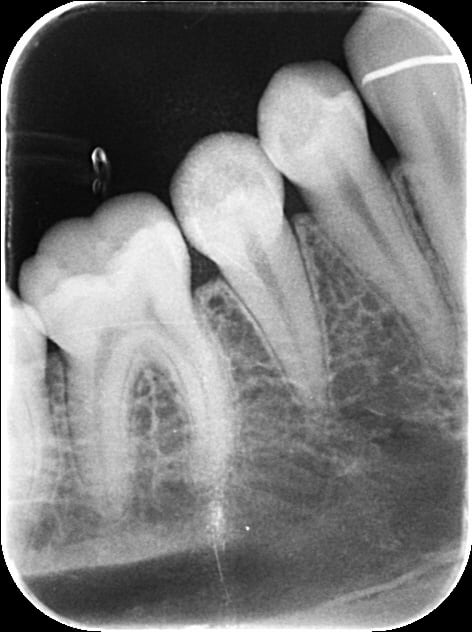

Un patient, jeune 20ans, qui vient en contrôle, 1ére fois, me dit qu'il a un kyste niveau 45/46, à surveiller, sans plus.

Je fais une pano et une rétro.

Est-ce la loge submandibulaire , j'ai un doute...l'image est bizarre. Quand pensez vous ?

Cone Beam....